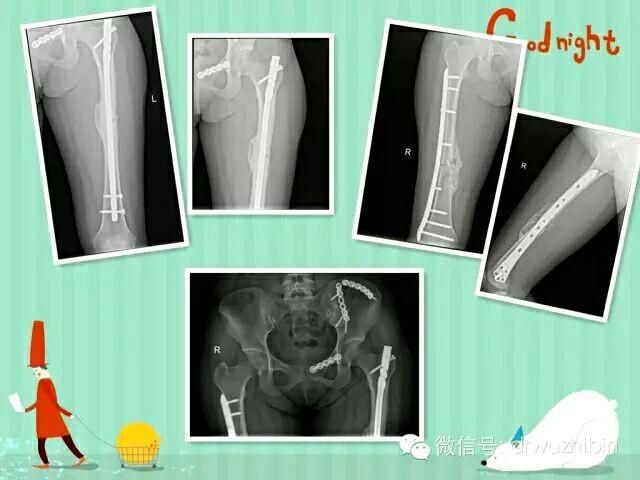

以下是近期收治的一名骨盆多發性骨折合并泌尿系損傷、雙側股骨幹骨折的患者,術後康複良好。